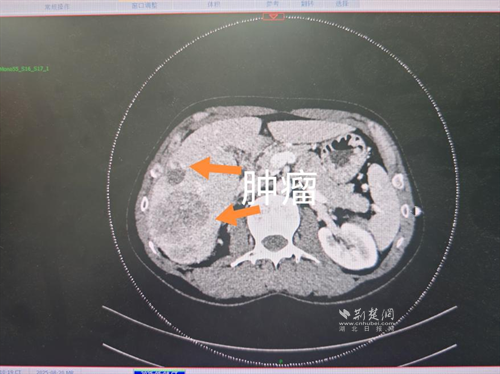

經(jīng)過肝膽外科牽頭組織的多學(xué)科MDT會診,團(tuán)隊(duì)確認(rèn)其適合接受當(dāng)前國際先進(jìn)的釔90樹脂微球選擇性內(nèi)放射治療。治療僅一個月后,患者病灶即從10cm縮小至6cm;術(shù)后六個月復(fù)查顯示,病灶體積進(jìn)一步縮小近40%,影像學(xué)檢查提示完全緩解,臨床分期成功轉(zhuǎn)化,達(dá)到手術(shù)切除標(biāo)準(zhǔn)。